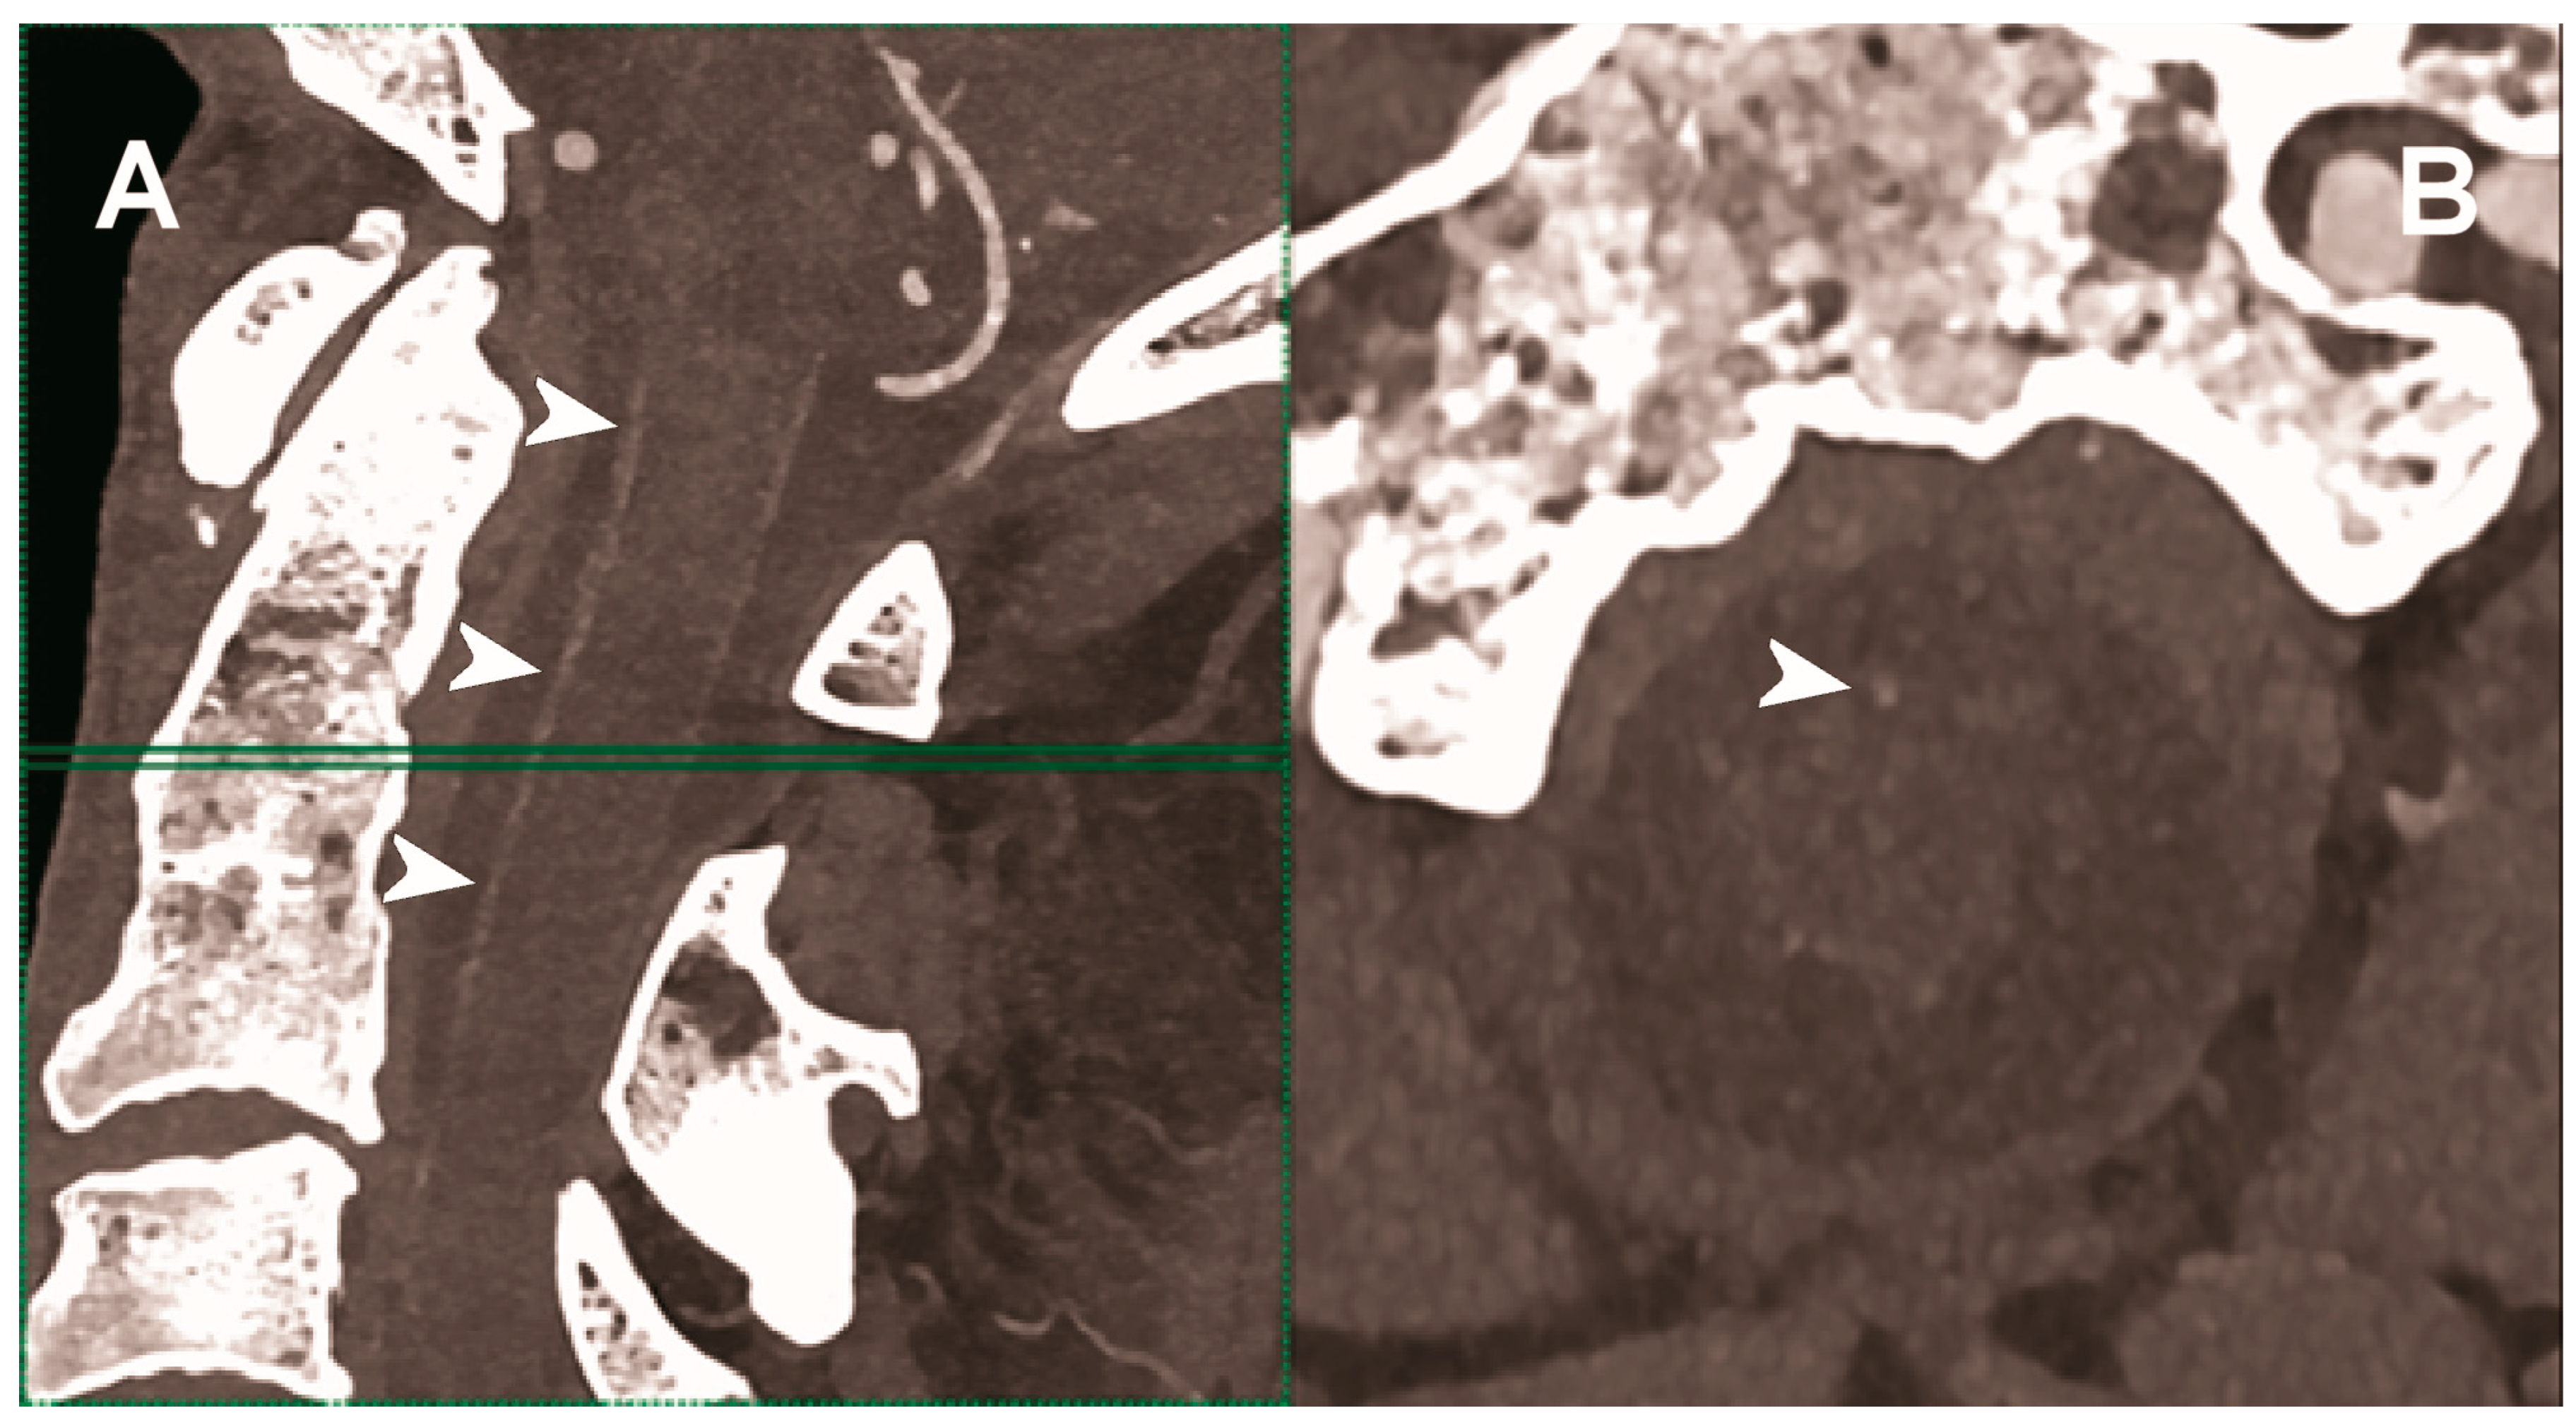

| Hetterich et al. 2014 [103] | Ex vivo (7 postmortem human carotid artery specimens). |

|

| Sartoretti et al. 2020 [104] | Ex vivo (carotid artery specimen of deceased male donor). | Improved lumen and plaque visualization and image noise with PCCT employing the multi-energy bin option in combination with tungsten as contrast media compared with the standard iodine. |